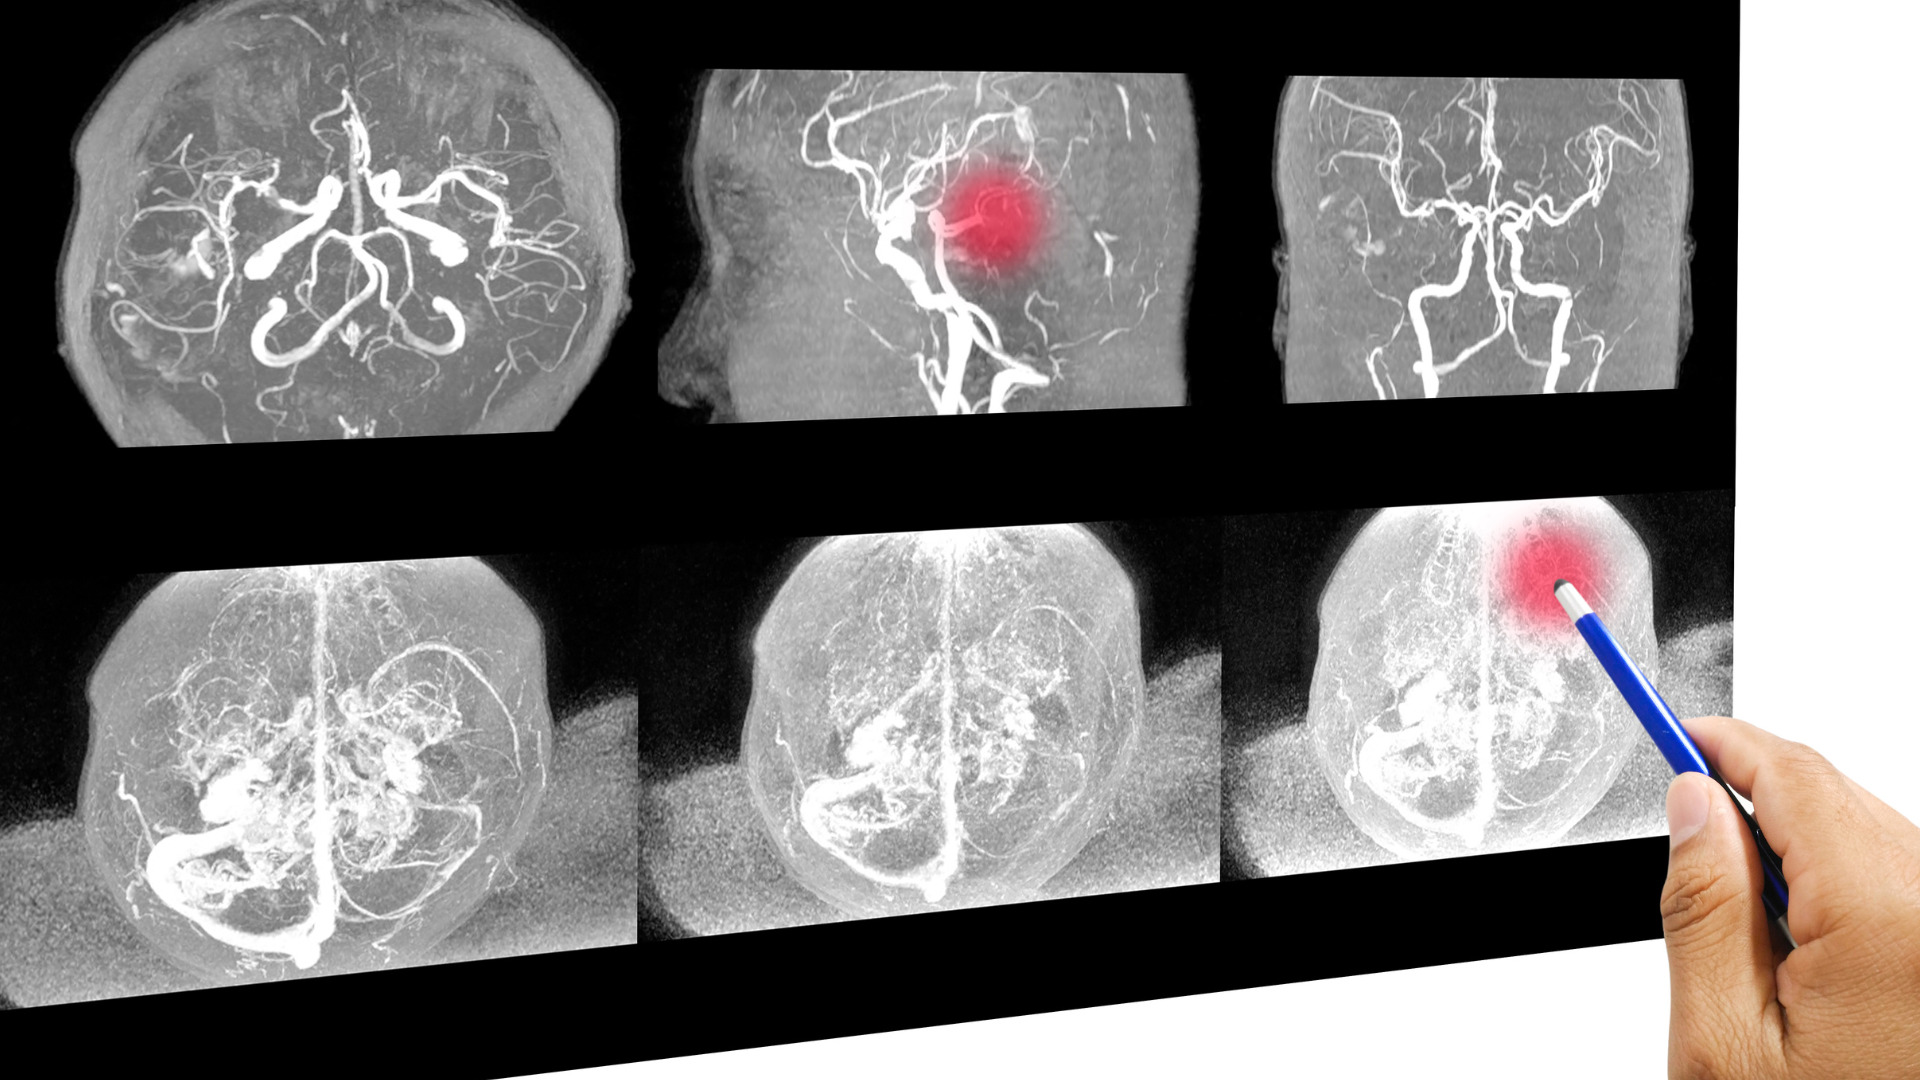

Chụp CT (chụp cắt lớp vi tính): Chụp CT giúp bác sĩ xem xét tình trạng máu rỉ trong não bộ. Kỹ thuật này sử dụng tia bức xạ X để tạo ra hình ảnh một mặt cắt ngang hoặc tạo ra hình ảnh chi tiết về lưu lượng máu trong động mạch não. Kỹ thuật chẩn đoán hình ảnh này sẽ thể hiện kích thước, vị trí và hình dạng của túi phình động mạch não.

Chụp MRI (chụp cộng hưởng từ): Kỹ thuật này sử dụng sóng vô tuyến để tạo ra hình ảnh chi tiết về động mạch não và có thể hiển thị kích thước, vị trí và hình dạng của túi phình động mạch.

Chụp động mạch não bằng máy DSA: Đây là một kỹ thuật can thiệp nội mạch với mục đích thu thập hình ảnh động mạch não. Kỹ thuật này sẽ giúp bác sĩ phát hiện những tắc nghẽn, xác định điểm yếu trong thành động mạch não, trong đó có túi phình mạch não.